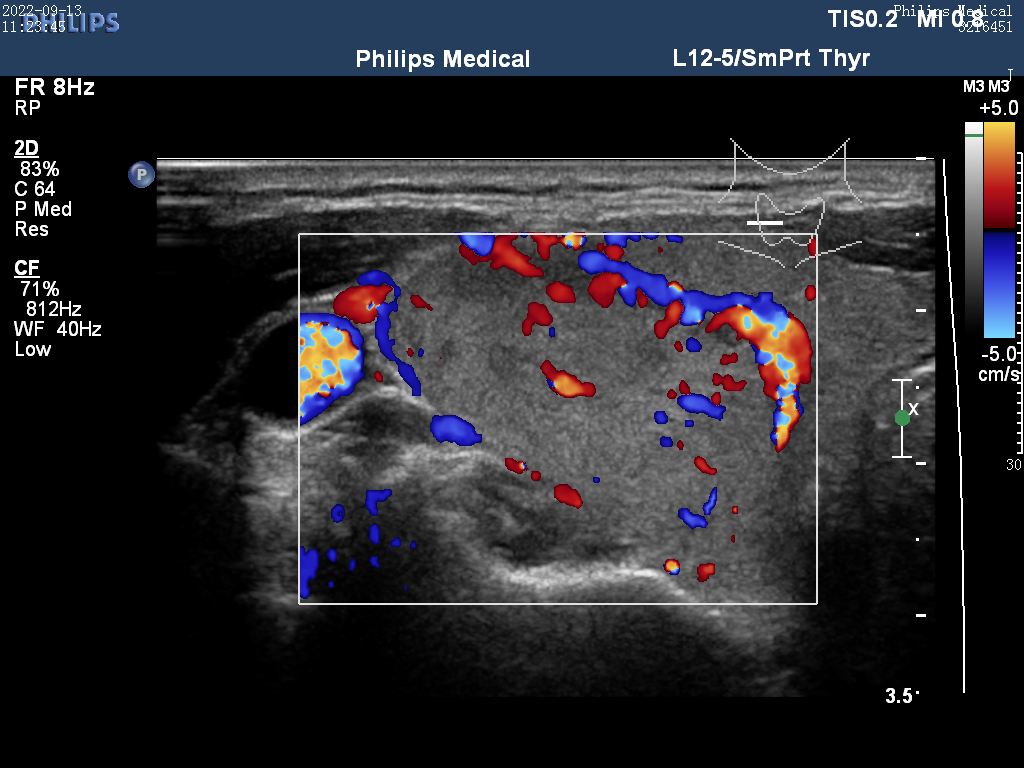

Ultrasound

ID: bac1d6e6-f51a-4d51-ae79-36c7f492e7e8...bac1d6e6-f51a-4d51-ae79-36c7f492e7e8

32 yoshli Ayol

13.01.2026 16:49

Yuqori

Tashxis

Malignant (Xavfli)

Saraton xavfi aniqlandi - Zudlik bilan onkolog va endokrinolog bilan bog'laning!

Ishonch

100,0%

TSH

100,0

Tugun

0,4 sm

Yuklab olingan (16x)

Ko'rish